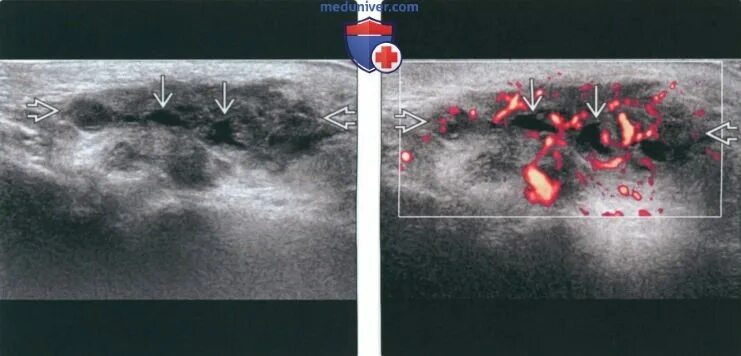

Метастазы в лимфоузлах форум